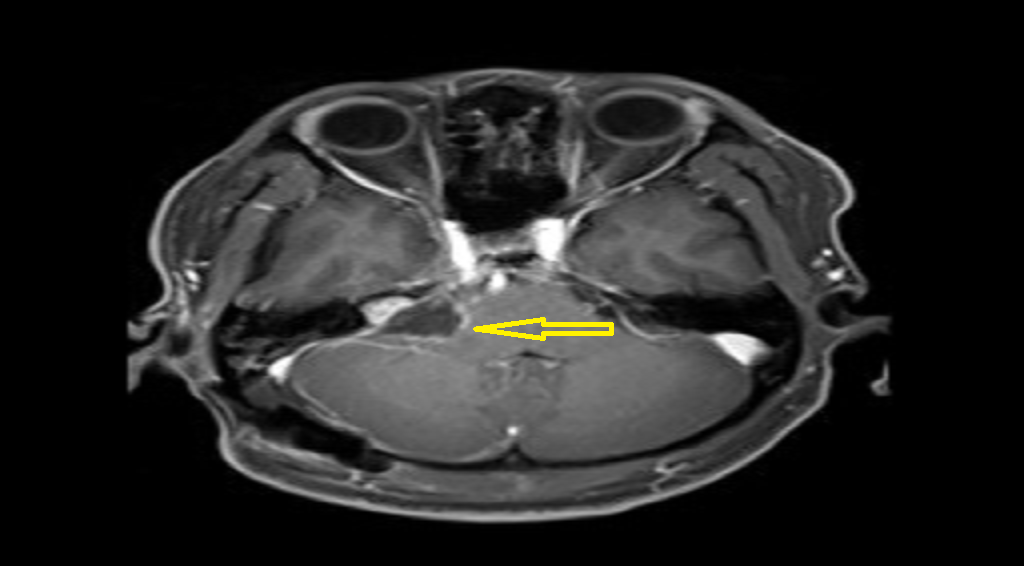

■ 王先生的肿瘤位于右侧桥小脑角区考虑为听神经瘤可能性大,虽然较王女士的肿瘤小,但该肿瘤已严重侵犯王先生内听道,还有瘤内出血现象,必须马上手术。术中手术医师全神贯注在电生理监测下细致地避开重要血管,将肿瘤组织与面听神经、三叉神经分离,成功将肿瘤完整切除。

(术后)